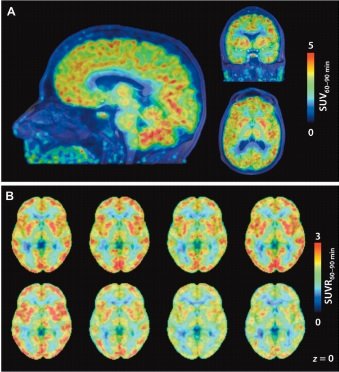

این تکنیک به آنها اجازه داده است، برای اولین بار یک تجسم از فعالیت فراوراثت (Epigenetic)، (مکانیزمی که بر بیان ژن تاثیرگذار است) در مغز یک انسان زنده را به دست آورند. این تکنیک میتواند در زمینه نشان دادن نقش فراوراثت در اختلالات مختلف کمک کننده باشد و حتا این پتانسیل را دارد تا در زمینه توسعه داروها برای درمان این بیماریها نیز کمک کننده باشد. فراوراثت در تغییر بیان ژن (gene expression) نقش دارد. ( خواه ژن را به جریان انداخته یا جریان آنرا متوقف کند.) فراوراثت با انواع مختلف بیماریها همچون اختلالات مغزی، آلزایمر، اسکیزوفرنی و افسردگی مرتبط است. جیکوب هوکر، رادیولوژیست دانشکده پزشکی هاروارد و نویسنده این روش عکسبرداری در این ارتباط گفته است: «قطع شدن ارتباط میان ژنها که شما آنها را از طریق وراثت از والدین خود به دست آوردهاید و تعاملی که آنها با زندگی شما دارند، منجر به وجود آمدن اتفاقات مختلفی میشود که یکی از این اتفاقات به وجود آمدن بیماریها است. هوکر و همکارانش به دنبال آن هستند تا درک خود در ارتباط با فراوراثت در مغز را بیشتر کنند. او در این ارتباط گفت: «به منظور انجام این کار، شما باید بتوانید راهکاری ابداع کنید که بر تنظیم فراوراثت در طول زندگی یک فرد نظارت کند. اینکه ما به انتظار بنشینیم تا فردی جان خود را از دست بدهد و سپس یک عکس فوری از بافت مغز او برداریم، بهطوری که پس از مرگ کشف کنیم، چه اتفاقی رخ داده است، هیچ سودی برای ما ندارد.» در مطالعه جدیدی که روز چهارشنبه در مجله Science Translational Medicine منتشر شده، محققان موفق شدند از چگالی یک نوع آنزیم به نام داستیلاز هیستون (HDACs) عکسبرداری کنند. این آنزیم به عنوان تنظیم کننده بیان ژن در مغز و وظایف مربوطه با آن شناخته شده است. چالش اصلی در این تکنیک به تصویر کشیدن این آنزیم در یک مغز زنده عنوان شده است. برای اینکار محققان یک عامل تصویربرداری رادیواکتیو به نام مارتینوستات (Martionosat) را طراحی کردند. این عامل به HDACs چسبیده و با استفاده از اسکن PET (توموگرافی تابش پوزیترون) موفق شده است HDACs را نشان دهد. این فناوری قبلا روی حیوانات مورد آزمایش قرار گرفته بود، اما این اولین باری است که روی یک انسان مورد استفاده قرار گرفته است. در تصاویر به دست آمده، مناطق قرمز رنگ نشان دهنده بیشترین تراکم HDACs و مناطق آبی رنگ کمترین تراکم HDACs را نشان میدهند.

در این مطالعه، محققان مغز هشت انسان بالغ سالم را بعد از تزریق مارتینوستات به مدت 90 دقیقه مورد عکسبرداری قرار دادند. هوکر در این ارتباط گفته است: «این تحقیق آنچنان که تصور میشود ساده نبود. این داروی رادیواکتیو تنها دارای طول عمر 20 دقیقه است. در نتیجه ما برای هر اسکن باید این دارو را تولید میکردیم. سالها طول کشید تا در مورد مولکولها و طراحی این تکنیک تصویربرداری اطلاعات لازم را به دست آوریم. بهطوری که از این اطلاعات برای توسعه داروی جدید استفاده کنیم.» هوکر گفته است عکسبرداری از مغز انسانهای سالم دور از انتظار نیست. او در این ارتباط گفت: «دیدن درجه غلظت HDACs در مغز این افراد، من را متحیر ساخته است. نکتهای که این تکنیک به ما آموخت این است که تنظیم داستیلاز هیستون در مغز از اهمیت بالایی برخوردار است. به دلیل اینکه باعث میشود مغز به درستی کار کند.»